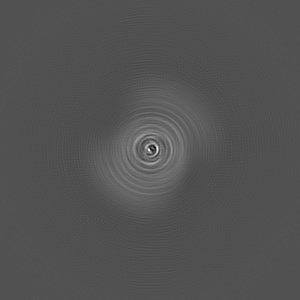

CryoEM Structure of 40-Residue Arctic (E22G) Beta-Amyloid Fibril Derived by Co-Analysis with Solid-State NMR | E22G Abeta40

Helical reconstruction2.5 Å